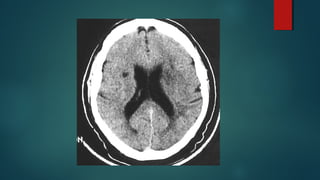

Este documento es el programa para un taller de imágenes del curso de emergencia 2015 impartido por el Dr. Víctor Delgado. El taller se centra en el uso de imágenes médicas para el diagnóstico y tratamiento de pacientes en coma traumático según la base de datos de Marshall. El Dr. Delgado es el único instructor repetido a lo largo del documento.